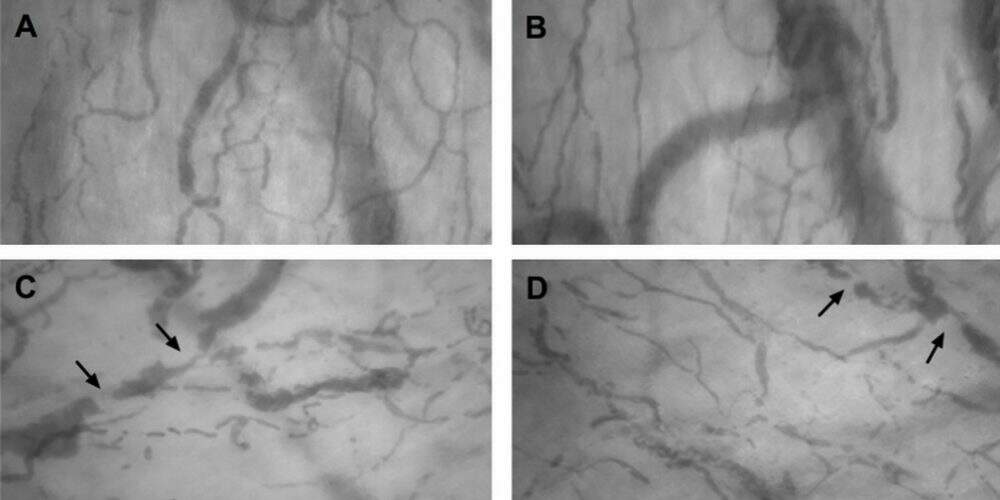

Pesquisadores de Ribeirão Preto registraram pela primeira vez os efeitos da Covid-19 no sistema circulatório. Um estudo publicado como prévia (pré-print) identificou a formação de coágulos microscópicos em pacientes mais graves da doença.

Segundo o artigo, de treze pacientes hospitalizados, onze apresentaram a formação de microtrombos – que impedem a circulação – nos pequenos vasos localizados embaixo da língua.

Essa foi a primeira vez que cientistas identificaram e conseguiram documentar os coágulos em pacientes vivos.

“Nossa investigação demonstrou trombos na microcirculação desde a início da hospitalização”, escreveram os cientistas.”Esse achado reforça que a trombose microvascular é uma característica da Covid-19.”